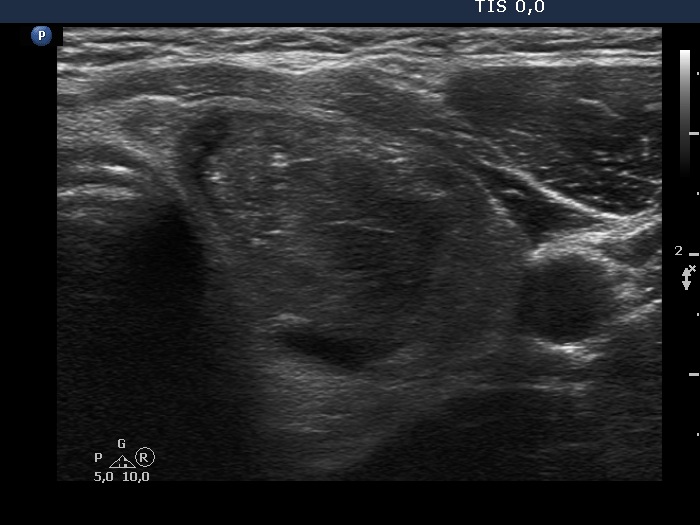

Second examination 7 years later (second row of images):

Clinical presentation. In the past 7 years, the patient had no complaints and therefore did not come to the proposed checkup either. Now he felt it was time to do an investigation.

Functional state: subclinical hypothyroidism with TSH 5.82 mIU/L, aTPO 98 U/mL.

Palpation: a hard nodule in the left lobe.

Ultrasonography. The presentation of the thyroid was essentially the same as 7 years ago. The only discrepancy was the lesion in the left lobe. Firstly, the size of the lesion have substantially increased to 25x18x25 mm (width, depth, and length, respectively), the volume was 5.89 mL which means that the volume became almost 8-times larger. Secondly, it was no more question whether the lesion was a pathological nodule or not. It turned out that this lesion is clearly a pathological nodule. Thirdly, in contrast to the former examination, the nodule has numerous microcalcifications and showed a clearly irregular, lobulated margins.

Aspiration cytology resulted in suspicion of papillary cancer.

Total thyroidectomy was performed, histopathology disclosed a T2 papillary cancer and Hashimoto's thyroiditis.